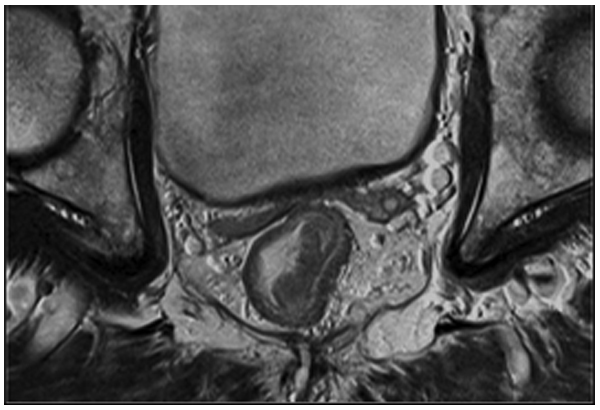

直肠癌的高分辨扫描图像